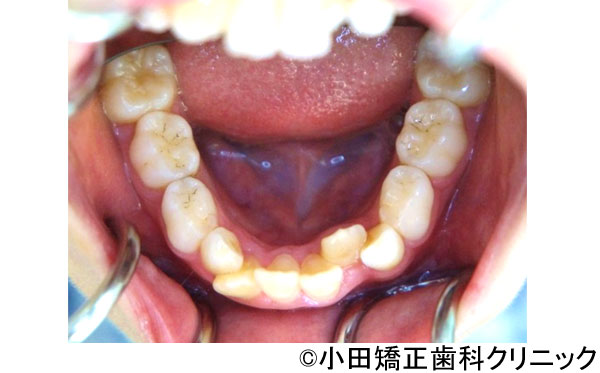

【症例4】口元が突出したいわゆる"クチゴボ"状態を、裏側(舌側)矯正で患者さんの期待を超えて治したい所を徹底的に治す治療

- 治療前

- 治療後

- 口元が突出したいわゆる"クチゴボ"状態を、裏側(舌側)矯正で患者さんの期待を超えて治したい所を徹底的に治す治療

- 患者様

- 26歳

- 費用

- 1,200,000円(税込)(上のみ舌側装置)

- 期間

- 2年

患者様の症状

-

口元が突出したいわゆる"クチゴボ"状態で、下あごの先に梅干し状のしわがあり、締まりがなく、顔全体との調和のない口元となっています。上下ともにでこぼこも認められます。

治療法

裏側矯正を用いて、上の横の歯2本と下の前歯1本を抜いて治療してまいります。

治療結果

美しい口元となり、顔全体とのバランスも良く、社会でコミュニケーションを図る時に人と面と向かって接する重要な顔立ちを大きく改善することができました。QOL(生活の質)を上げることができたと思います。治療が進んで顔立ちがきれいに変わっていくことで、診療室に入って来られても、最初の印象から誰だかすぐにわからないことがありました。